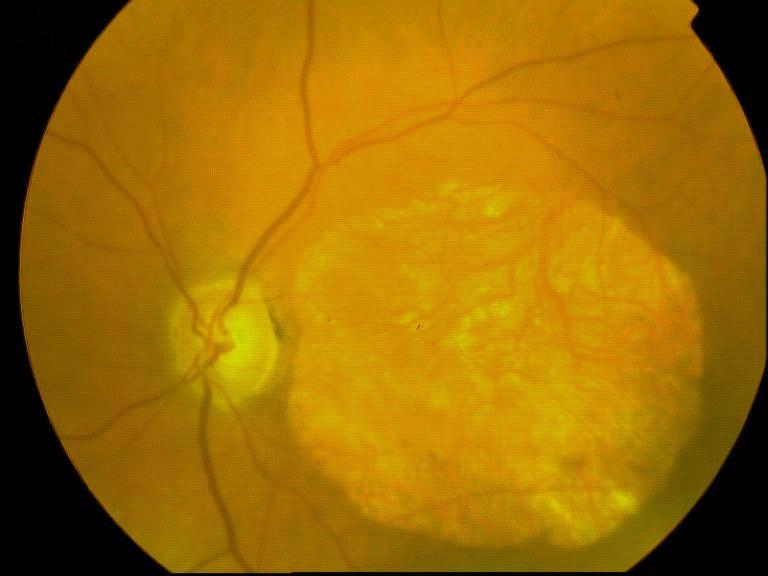

CICATRICE APRES EXERESE CHIRURGICALE DE NEOVAISSEAUX

IM000008.JPG